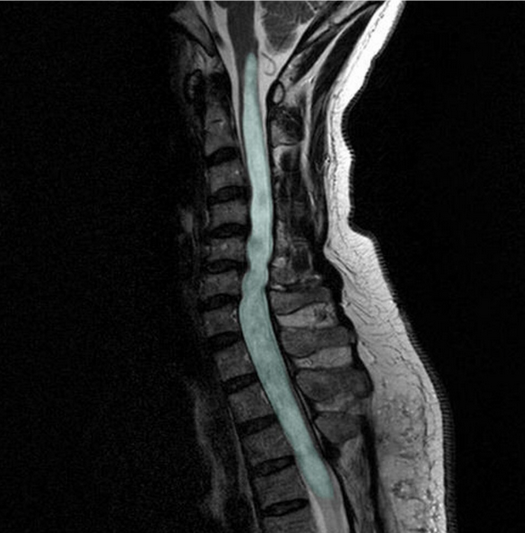

Syringomyelia

Syringomyelia is a disorder characterized by the formation of an abnormal, fluid-filled cavity (syrinx) within the central canal or parenchyma of the spinal cord. The syrinx develops due to disrupted cerebrospinal fluid (CSF) flow, most commonly at the craniocervical junction. Progressive expansion leads to compression and destruction of spinal cord pathways, classically beginning with decussating spinothalamic fibers. When the cavity extends into the brainstem, the condition is termed syringobulbia.

• Perform MRI using sagittal and axial T1- and T2-weighted sequences.

• Identify the syrinx as a CSF-intensity cavity within the spinal cord.

• Document:

• Maximum anteroposterior diameter of the syrinx (mm)

• Cranio-caudal extent (vertebral levels involved)

• Location (central vs eccentric)

• Presence of septations

Figure 1. in: Shunting of recurrent post-traumatic syringomyelia into the fourth ventricle: a case report” by Chih-Lung Lin, Journal of Medical Case Reports, licensed under CC BY 2.0.